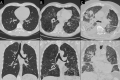

Figures